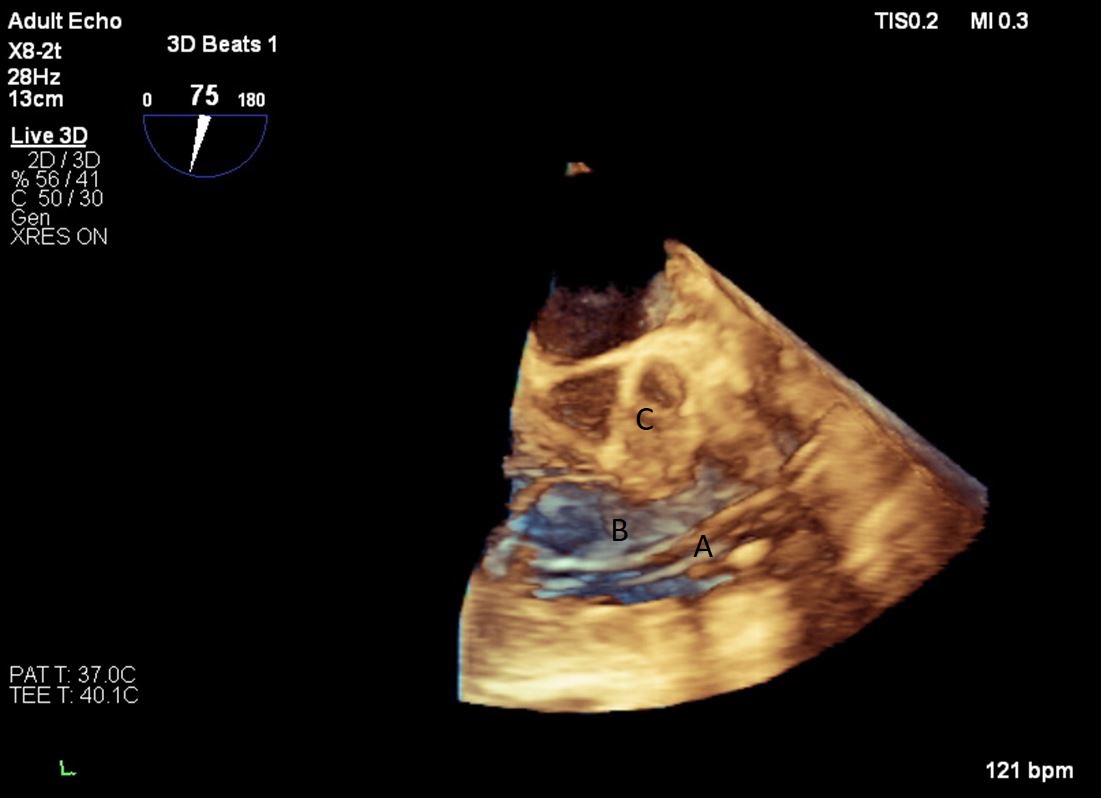

Both TTE and TEE can help with ideal positioning of the Impella (Figs. 5,6). The distance from the aortic valve to the Impella inlet should be measured. This should ideally be 3.5–4 cm for all Impella devices except for the Impella 5.5 for which it is 5 cm [15] (Fig. 7). The outlet should be 1.5–2 cm above the sinuses of Valsalva. The catheter should be angled towards the LV apex and away from the septum and mitral valve. The positioning of both the inlet in the LV cavity and the outlet above the aortic valve should be confirmed. Color flow doppler imaging can help confirm this positioning as a mosaic pattern will be visualized near the inlet and outlet ports on spectral doppler (Fig. 8). Real-time 3D echocardiography can also be used to help in visualizing Impella positioning relative to other anatomical structures (Fig. 9). After placement of the Impella, the aortic and mitral valves should be interrogated for any new or worsening regurgitation or dysfunction [16]. TEE can also help identify additional complications of Impella placement including pericardial effusion or LV free wall rupture [17].

Fig. 15.Real time 3D TEE imaging of the RV inflow outflow view demonstrating the Protek Duo in the RVOT. (A) Protek Duo. (B) RVOT. (C) Aortic valve.